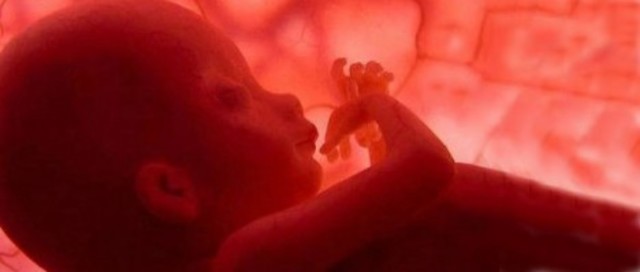

En este momento su piel es semitranslúcida de lo extremadamente fina que es, tanto que incluso puedes ver las venas y arterias.

el bebé ha alcanzado una forma y una proporción prácticamente humanas. Puede llegar a medir 15 cm de media y pesar hasta 250 gr. La piel de la futura mamá empieza a estirarse de forma más pronunciada y la posición del útero llega a alcanzar la altura del ombligo.

El sistema respiratorio comienza a ensayar pequeños movimientos de respiración,casi todos sus órganos sensoriales han alcanzado un alto grado de madurez a excepción de la vista, la cual tardará varios meses después de su nacimiento en estar completamente desarrollada. No obstante, sí que es capaz de percibir ciertos brillos y cambios de luz a través de la piel de la madre.

En esta semana, el bebé aprende a abrir y cerrar los ojos. Este movimiento es precursor del reflejo del parpadeo.